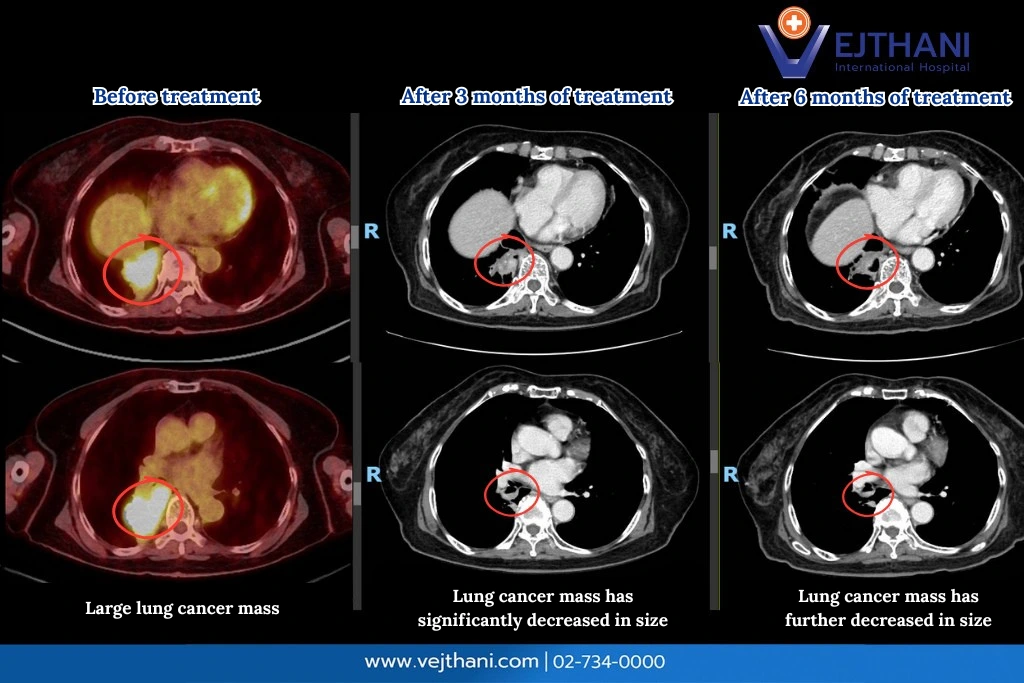

CT scan images highlighting RET fusion lung cancer and precise treatment using Next-Generation Sequencing (NGS) at Vejthani International Hospital.

Follow-up imaging demonstrated clear benefits from this treatment:

• Before treatment: The lung tumor was large.

• After 3 months of treatment: The tumor had significantly decreased in size.

• After 6 months of treatment: The tumor had shrunk even further, showing a strong and sustained response.